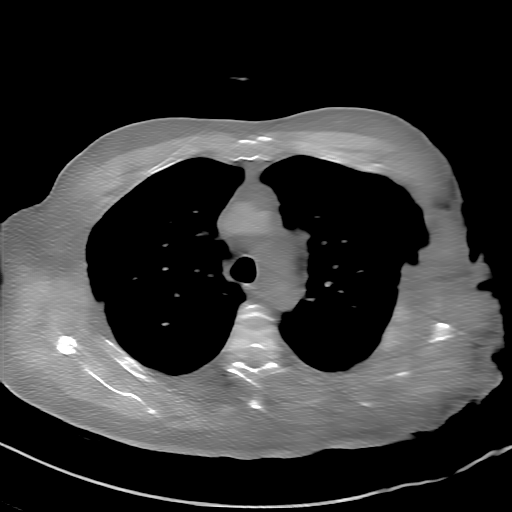

GT

FBP

HQS-CG

DuDoNet

Meta

Meta_re

EPNet

Qualitative Results Comparison. We also visualize the reconstruction results of these methods on AAPM-test and COVID-test datasets. As in the first three rows of Fig. 4, the reconstructed images from ours and retrained MetaInvNet show the best visualization quality on AAPM-test set across different angle numbers. Besides, our results show sharper details with the additional utilization of in the projection domain. When testing the reconstructed image on the COVID-test set, our result also gives sharper details but with more artifacts since the data distribution is very different. Although HQS-CG has achieved better quantitative results on the COVID-test dataset, the reconstructed image of their model in the fourth row is even smoother than FBP.